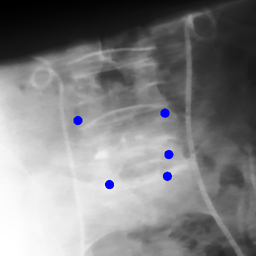

The dataset we use in the experiments is a cone-beam CT (CBCT) dataset captured for radiation therapy. The dataset contains 340 raw CBCT scans with each has 780 X-ray images. Each X-ray image comes with a geometry file that provides the registration ground truth as well as the information to reconstruct the CBCT volume. Each CBCT volume is reconstructed from the 780 X-ray images, and in total, we have 340 CBCT volumes (one for each CBCT scan). We use 300 scans for training and validation, and 40 scans for testing. The size of the CBCT volumes is 448×448×768448448768448\times 448\times 768 with 0.5 mm voxel spacing, and the size of the X-ray images is 512×512512512512\times 512 with 0.388 mm pixel spacing. During the experiments, the CBCT volumes are treated as the 3D pre-intervention data, and the corresponding X-ray images are treated as the 2D intra-intervention data. Sample X-ray images from our dataset are shown in Figure. Note that unlike many existing approaches [15, 17, 25] that evaluate their methods on small datasets (typically about 10 scans) which are captured under relatively ideal scenarios, we use a significantly larger dataset with complex clinical settings, e.g., diverse field-of-views, surgical instruments/implants, various image contrast and quality, etc.

We consider two common views during the experiment: the anterior-posterior view and the lateral view. Hence, only X-rays that are close to (±5°plus-or-minus5°\pm 5\degree) these views are used for training and testing. Note that this selection does not tightly constrain the diversity of the X-rays as the patient may be subject to movements with regard to the operating bed. To train the proposed method, X-ray and DRR pairs are selected and generated with a maximum of 10°10°10\degree rotation offset and 202020 mm translation offset. We first invert all the raw X-ray images and then apply histogram equalization to both the inverted X-ray images and DRRs to facilitate the similarity measurement. For each of the scan, we also annotate their landmarks on the reconstructed CBCT volume for further evaluation.

Refer to caption

Figure 6: Sample raw X-ray images of our dataset.